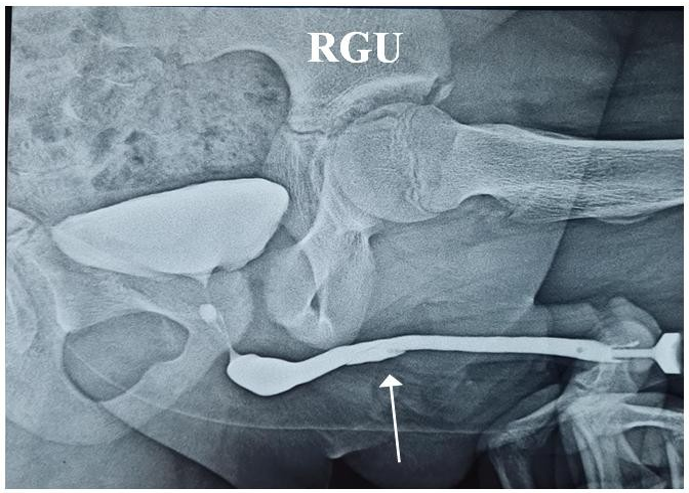

Figure 2: Pre-Operative RGU of Patient Showing Anterior Urethral Valve

An 11-year-old boy presented with severe dysuria and difficulty voiding for 4 days, with a long-standing history of weak urinary stream for 3 years. He had no prior urethral instrumentation, urinary tract infections, or perinatal complications. Antenatal ultrasound was normal. Urine examination was unremarkable and serum creatinine was 1 mg/dL. Ultrasonography showed mild bladder wall thickening without hydroureteronephrosis and bilaterally normal kidneys. Uroflowmetry demonstrated a voided volume of 240 mL and Qmax of 4 mL/s. Micturating cystourethrogram (MCU) revealed a dilated posterior urethra consistent with posterior urethral valve (PUV), along with abrupt tapering of the anterior urethra, suggesting an anterior urethral valve (AUV).

AUVs most commonly occur in the bulbar urethra (40%), followed by the penoscrotal junction and pendulous urethra. Clinical presentation of combined PUV and AUV is variable, ranging from neonatal bladder outlet obstruction to late-childhood symptoms such as poor stream, straining, incontinence, or recurrent infections. MCU remains the most useful initial investigation because it can demonstrate both posterior dilation and anterior urethral caliber change. Endoscopic valve ablation is the treatment of choice and usually results in symptom resolution.